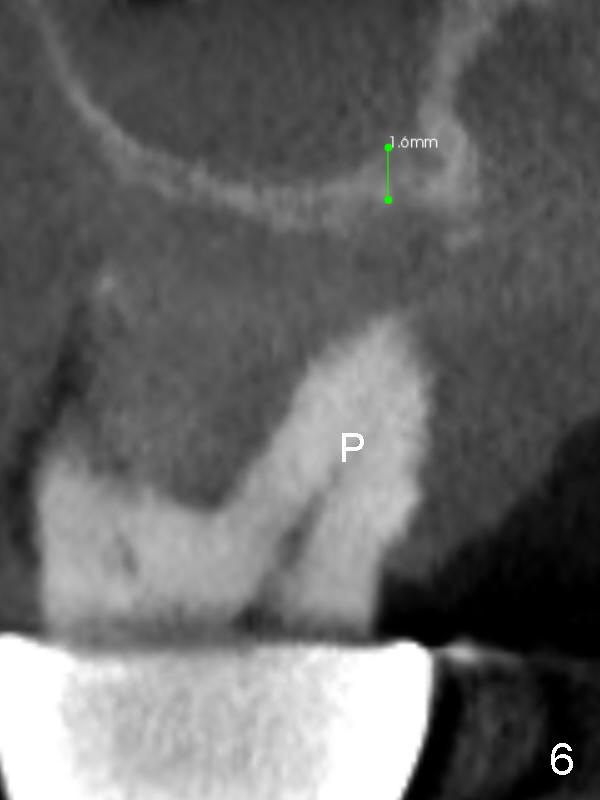

The posterior abutment of the 5-unit FPD, #15 is loose with the buccal roots extruded outside the sockets. The palatal socket is the appropriate site of immediate implant with the presence of the buccomesio-palatal walls, although short. The thinnest portion of the palatal socket is 1.6 mm (Fig.6 CBCT coronal section through the palatal root (P)). Magic Sinus Lifter cannot break through the sinus floor. UF drills are used to create osteotomy and sinus lift until 4.3 mm. A 5 mm tap drill is inserted without stability (Fig.1). A 5.5x9 mm IBS dummy implant achieves insertion torque of 10 Ncm, although it looks smaller (Fig.2) than the tap in Fig.1. After placement of PRF membrane and bone graft (allograft, autogenous bone and Osteogen, Fig.3 *), a 6x9 mm IBS implant is placed with insertion torque of 30 Ncm. It appears that the fins of the implant slice into the bone at high magnification for engagement. Following further placement of the implant, bone graft is packed into the distal portion of the socket (Fig.4 <). The thin fins extends into mesial and distal thicker bone (Fig.5 (CBCT sagittal view) *).